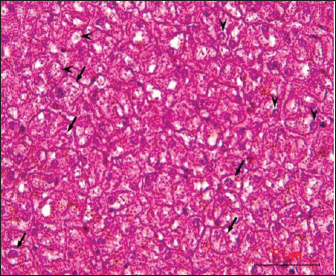

Post-mortem examination resultsPost-mortem examinations of the dead horses infected with M. haemofelis revealed signs of overall emaciation in the affected animals, paleness of internal organs (Fig. 5), and prominent splenomegaly. The liver, kidneys were enlarged; however, the heart showed white patches. Moreover, histopathological changes were characterized by different histopathological changes of eosinophilic degeneration of cardiac muscle fibers, accompanied by atrophy in some fibers, with bleeding between fibers, besides atrophic glomeruli, accompanied with the dilatation of renal tubules in the kidneys, as well as marked reduction in the proportion of white pulp of splenic tissue and degenerative changes in the cytoplasm of hepatocytes, accompanied by nuclear alterations characterized by loss of chromatin content in the hepatic tissue (Figs. 6–9).

Fig. 9. sections demonstrated degenerative changes in the cytoplasm of hepatocytes (arrows), accompanied by nuclear alterations characterized by loss of chromatin content (arrowhead), H&E, 40x. Scale bar=5µm. DiscussionIn this study, multiple methods were used to diagnose the disease and identify the causative agent in infected horses. Despite the variety of diagnostic approaches and slight differences in their accuracy, they remain among the most reliable options in this context. Generally, it can be said that Giemsa-stained blood smears help diagnose various conditions by enabling microscopic identification of blood cells, microorganisms, and other abnormalities. Key diagnostic uses include the definitive identification of blood parasites through thick and thin blood films. Additionally, they are useful for investigating anemia by examining red blood cell morphology and diagnosing leukocyte abnormalities and other blood cell disorders by detecting abnormal cells and features. Nonetheless, Giemsa-stained blood smears allow the assessment of red blood cell size, color, and other characteristics to help diagnose various types of anemia (Woronzoff-Dashkoff, 2002; Stockham and Scott, 2025). On the other hand, Acridine orange blood smear diagnosis is a quick, fluorescence microscopy-based technique that detects nucleic acids (DNA and RNA) in blood, enabling rapid identification of most blood parasites, blood-borne bacteria, and protozoa. The dye highlights DNA in yellow-green and RNA in bright red, facilitating rapid screening and potential early diagnosis of infections. However, some limitations include the inability to preserve the smears and potential issues with low parasitemia or specific organisms. Additionally, the method is based on enzymatic labeling and modified nucleotides, utilizing nicks in the DNA of mycoplasmas. Modified nucleotides are incorporated into the mycoplasmas' DNA and subsequently visualized through immunofluorescence microscopy. This approach is strain-independent, does not heavily stain nuclear DNA, does not stain other bacteria, and offers higher sensitivity than direct labeling methods using DAPI or Hoechst dyes (Ciancaglini et al., 2005; Ligasová et al., 2019). Hereby, the results indicated a high infection rate, which may confirm that relying on the cytological method in diagnosis may be acceptable from a scientific and practical standpoint. The main benefit of real-time PCR assays is their ability to accurately quantify target nucleic acids. The detection mechanism of a real-time PCR system also enhances the assay's sensitivity (Artikai, 2022; Martineau et al., 2023). Additionally, quantitative real-time PCR has transformed molecular diagnostics with its simplicity, increased sensitivity and specificity, and quick turnaround time. However, quantitative PCR-based assays provide a clear advantage over other serological or conventional diagnostic methods (Ajaj et al., 2025). Over the past few decades, qPCR technology has gradually replaced several culture methods. Instead of relying on cytological or antigen-based data to identify pathogens, qPCR works by deliberately amplifying DNA fragments unique to a pathogen’s genome. The method is both accurate and fast. Unlike culture methods, which can take days to provide results, qPCR tests can be completed within hours. However, potential technical shortcomings that may affect assay performance and lead to false results include inadequate sample storage, problems with the preparation and quality of nucleic acids, poor selection of reverse-transcription primers and probes for PCR, and improper data analysis and statistical methods (Artika et al., 2020). In general, cytology can give false positives and whereas qPCR might miss low DNA samples. The acute phase response is a vital protective physiological reaction to infection, injury, and stress, aimed at restoring homeostasis by containing and destroying pathogens, removing damaged tissue, and promoting repair. In the present study, acute-phase responses were investigated by estimating haptoglobin, fibrinogen, and C-reactive protein levels (Cary et al., 2009; Vilhena et al., 2018). It was documented that in hemolytic anemia, red blood cells are destroyed prematurely, releasing hemoglobin into the bloodstream. Haptoglobin, a protein produced by the liver, binds to this free hemoglobin. When there is extensive red blood cell destruction, haptoglobin levels become depleted, leading to low haptoglobin levels in the blood, which is considered a key indicator of hemolytic anemia (as indicated in the current study). A low haptoglobin level indicates that red blood cells are being destroyed, although it doesn't specify the cause (Jain et al., 2011). Moreover, Korman et al. (2012) found that in Hemomycoplasma infection, there was a trend for decreased haptoglobin concentrations, likely because circulating haptoglobin complexes with hemoglobin, causing transient decreases in haptoglobin during hemolysis. Furthermore, Fibrinogen is a vital part of the acute phase response, acting as a classic acute phase reactant that significantly increases or decreases (through liberation or consumption) during inflammation and injury to form a protective fibrin clot at the injury site. This clot helps contain blood loss, prevents microbial infection, and provides a framework for immune cells and fibroblasts to kick-start tissue repair. Fibrinogen also affects leukocyte function and transmigration, supporting the inflammatory response and helping to resolve tissue damage, Thrall (2012). Conversely, Muszbek et al. (2008) noted that hypofibrinogenemia might indicate early hepatic failure or insufficiency when liver functions decline, while hyperfibrinolysis, decreased fibrinogen synthesis, and increased fibrinogen consumption occur when disseminated intravascular coagulation has been triggered. It has been shown that C-reactive protein (CRP) is a substance produced by the liver in response to inflammation, and it is often used as a marker of inflammation in the body. Generally, significantly increasing its levels could indicate infection and cardiac risk Mouliou (2023). Furthermore, High CRP levels may mean an acute or chronic health condition, such as infections from bacteria or viruses. Additionally, Arfuso et al. (2023) added that abnormal CRP values indicate an increased risk of clotting or bleeding disorders. Thereby, it can be concluded that the evaluation of acute phase response is indeed an aid to the diagnosis of diseases causing anemia and tissue damage, as confirmed in this study. The importance of diagnostic criteria of postmortem diagnosis on both macro- and micro diagnosis of the dead carcasses is crucial in animals for several reasons, including determining the cause of death, identifying disease outbreaks in herds, safeguarding public and animal health by detecting zoonotic diseases, contributing to quality assurance, and providing closure for owners. A thorough postmortem helps veterinarians solve problems on farms, prevent future illnesses, and make informed decisions about animal welfare and herd management (Al Matwari et al., 2022; Martineau et al., 2023; De Oliveira Battisti et al., 2024). In the present study, the results of the autopsy of horses that died as a result of infection with equine Hemomycoplasmosis proved that the animals suffered from clear signs of anemia, in addition to gross and microscopic changes in various parts of the animal’s body, concentrated in the liver, spleen, kidneys and heart, which proves the great pathological effects caused by this disease. This is also noted by others (Dieckmann et al., 2012; Diab et al., 2017; Ballados-González et al., 2025). The evidence from this study supports the recommendation for practical diagnosis that cytological diagnosis is still advised for field screening; on the other hand, qPCR is recommended as a confirmatory diagnosis. LimitationsThe study did not include RCO analysis: a graphical method to evaluate a classification model's performance as both cytology and qPCR are binary (positive/negative) tests rather than continuous quantitative assays, making traditional ROC curve construction less applicable. AcknowledgmentsThe authors highly appreciated the assistance of the College of Veterinary Medicine, University of Basrah, Iraq. Conflict of interestThe authors confirm that there is no conflict of interest in this scientific article. FundingThe College of Veterinary Medicine, University of Basrah, Iraq, was responsible for the financial support provided for this scientific research. Authors' contributionsAll authors have reviewed, discussed, and agreed on their individual contributions before and during the submission of their article. The first author, ALI JARAD, performed sample collection and laboratory analyses as well as organized and prepared research data. Further, gathered and reviewed the scientific literature used in the study. Alsaad K.M., the second author, conducted the statistical analyses. Writing the original draft as well as preparing and writing the full manuscript. Data availabilityAvailable from the corresponding author upon reasonable request. ReferencesAbed, F.A. and Alsaad, K.M. 2017. Clinical, Hematological And Diagnostic Studies of Hemomycoplasma Infection (Mycoplasma ovis) in Sheep of Basrah Governorate. BasJVetRes 16(2), 284–301. Ajaj, E.A., Al-Farwachi, M.I. and Albadrani, B.A. 2025. Molecular detection of Hemotropic mycoplasma in stray dogs in Mosul city. Iraqi J. Vet. Sci. 39(2), 313–317. Al Matwari, E.H., Ahmed, J.A. and Al Saad, K. 2022. Hemomycoplasmosis (Eperythrozoonosis) in domestic animals (a review). IOSR 15(7), 14–19. Arfuso, F., Piccione, G., Guttadauro, A., Monteverde, V., Giudice, E. and Giannetto, C. 2023. Serum C-reactive Protein and Protein Electrophoretic Pattern Correlated with Age in Horses. J. Equine Vet. Sci. 126, 104561. Artika, I.M., Wiyatno, A. and Ma'Roef, C.N. 2020. Pathogenic viruses: molecular detection and characterization. Infect. Genet. Evol. 81, 104215. ArtikaI, I.M., ArtikaYora, M.P., Yora, D.P., Ungke, D. and Jaya, A. 2022. Real-Time Polymerase Chain Reaction Basic Principles and Current Applications. Genes 13, 2387. Atharv, M., Yash, B., Bandal MR Gole., Kadam, A. and Anjum, A. 2023. Elisa: the Immunological Diagnostic Tool. Iarjset 10(11), 1588–2394. Ballados-González, G.G., Cruz-Romero, A., Martínez-Hernández, J.M., Aguilar-Domínguez, M., Vieira, R.F.C., Grostieta, E., Becker, I. and Sánchez-Montes, S. 2025. Confirmation of the presence of Hemotropic Mycoplasma species in working equids from Veracruz, Mexico. Trop. Anim. Health. Prod. 19(575), 225. Bancroft, J.D., Suvarna, K.S. and Layton, C. 2018. (Eds). Bancroft‘s theory and practice of histological techniques E-Book .Elsevier Health Sciences. Beus, K., Goudarztalejerdi, A. and Sazmand, A. 2024. Molecular detection and identification of Hemotropic Mycoplasma species in dogs and their ectoparasites in Iran. Sci. Rep. 5(141), 580. Cray, C., Zaias, J. and Altman, N.H. 2009. Acute Phase Response in Animals: a Review. Comp. Med. 59(6), 517–526. Ciancaglini, E., Fazii, P. and Sforza, G.R. 2005. The use of differential fluorescent staining method to detect bacteriuria. Clin. Lab. 50(11-12), 685–688. Constable, P.D., Hinchcliff, K.W., Done, S.H. and Grunberg, W. 2017. Veterinary Medicine. A textbook of the diseases of cattle, sheep, goats, and horses. 11th ed. USA: WB Saunders Co. De Oliveira Battisti, L., Mongruel, A.C.B., Fagundes-Moreira, R., Baggio-Souza, V., De Souza, V.K.,De Amorim, D.B., Wagner, P.G.C., Souza, U.A.,Gonçalves, A.P., Girotto-Soares, A., De Faria Valle, S., André, M.R. and Soares, J.F. 2024. Postmortemdetection of hemoplasmas (hemotropic Mycoplasma spp.) in South American fur seal (Arctocephalus australis) sampled in Rio Grande do Sul State, southern Brazil. Comparative Immunol. Microbiol. Infect. Dis. 109, 102187. Diab, S.S., Poppenga, R. and Uzal, F.A. 2017. Sudden death in racehorses: postmortem examination protocol. J. Vet. Diag. Invest. 29(4), 442–449. Dieckmann, S.M., Hoelzle, K., Dieckmann, M.P., Straube, I., Hofmann-Lehmann, R. and Hoelzle, L.E. 2012. Occurrence of hemotrophic mycoplasmas in horses with correlation to hematological findings. Vet. Microbiol. 160(1-2), 43–52. Esmaeel, S. and Albadrani, B. 2019. Prevalence and some risk factors of bovine heamotropic mycoplasma in Nineveh province-Iraq. Iraqi J. Vet. Sci. 33(2), 427–431. Jain, S., Gautam, V. and Naseem, S. 2011. Acute-phase proteins: as a diagnostic tool. J. Pharm. Bioallied Sci. 3(1), 118–127. Jarad, A. and Alsaad, K.M. 2016. Clinical, Hematological And Diagnostic Studies Of Mycoplasma Wenyonii Infection In Cattle Of Basrah Governorate Basrah, Iraq. BasJVetRes 15(4), 37–53. Kinoshita, Y., Niwa, H., Uchida-Fujii, E. and Ueno, T. 2024. A real-time PCR assay for the quantification of Mycoplasma equirhinis in tracheal wash samples from Thoroughbred horses. J. Vet. Diagn. Invest. 36(1), 108–111. Korman, R.M., Cerón, J.J., Knowles, T.G., Barker, E.N., Eckersall, P.D. and Tasker, S. 2012. Acute phase response to Mycoplasma haemofelis and ‘Candidatus Mycoplasma haemominutum’ infection in FIV-infected and non-FIV-infected cats. Vet. J. 193(2), 433–438. Leech, N., Barrett, K., Morgan, G.A. 2015. SPSS for intermediate statistics: Use and interpretation: USA: Routledge. 5th ed. Routledge Ligasová, A., Vydržalová, M., Buriánová, R., Brůčková, L., Večeřová, R., Janošťáková, A. and Koberna, K. 2019. A New Sensitive Method for the Detection of Mycoplasmas Using Fluorescence Microscopy. Cells 8(12), 1510. Mandal. 2025. Textbook of veterinary parasitology. Singapore, Springer Nature Singapore Pte Ltd. Martineau, M., Castagnet, S., Kokabi, E., Tricot, A., Jaÿ, M., Léon, A. and Tardy, F. 2023. Detection of Mycoplasma spp. in horses with respiratory disorders. Equine Vet. J. 55(5), 747–754. Martineau, M., Kokabi, E., Taiebi, A., Lefebvre, S., Pradier, S., Jaÿ, M., Tardy, F. and Leon, A. 2023. Epidemiology and pathogenicity of Mycoplasma equirhinis in equine respiratory disorders. Vet. Microbiol. 287, 109926. Messick, J.B. 2004. Hemotrophic mycoplasmas (hemoplasmas): a review and new insights into 167 pathogenic potential. Vet. Clin. Pathol. 33(2), 2. Mouliou, D.S. 2023. C-Reactive Protein: pathophysiology, Diagnosis, False Test Results and a Novel Diagnostic Algorithm for Clinicians. Diseases 1(4), 132. Muszbek, L., Bagoly, Z., Bereczky, Z. and Katona, E. 2008. The involvement of blood coagulation factor XIII in fibrinolysis and thrombosis. Cardiovasc. Hematol. Agents. Med. Chem. 6(3), 190–205. Neimark, H., Johansson, K.E., Rikihisa, Y. and Tully, J.G. 2001. Proposal to transfer to some members of the genera Heamobartonella and Eperythrozoon to the genus Mycoplasma with descriptions of "Candidatus Mycoplasma haemofelis" "Candidatus Mycoplasma haemomuris""Candidatus Mycoplasma haemosuis and "Candidatus Mycoplasma wenyonii". Int. J. Syst. Evol. Microbiol. 51 (Pt 3), 891–899. Novacco, M., Wolf-Jäckel, G., Riond, B. and Hofmann-Lehmann, R. 2012. Humoral immune response to a recombinant hemoplasma antigen in experimental ‘Candidatus Mycoplasma turicensis’ infection. Vet. Microbiol. 157(3-4), 464–470. Saki, C.E. 2009. Clinical Eperythrozoon wenyoni (Adler and Ellenbogan,1934) and Heamobartonella bovis (Donatin) and Lestoquard,1934) infection in a cattle. F. Ü. SagBil. Vet. Derg. 23(2), 117–118. Stockham, S.L and Scott, M.A. 2025. Fundamentals of veterinary clinical pathology, 3rd. Charlotte, NC: Wily. Tasker S. 2022. Hemotropic mycoplasma. Vet. Clin. North Am. Small Anim. Pract. 52(6), 1319–1340. Tasker, S., Hofmann-Lehmann, R., Belák, S., Frymus, T., Addie, D.D., Pennisi, M.G., Boucraut-Baralon, C., Egberink, H., Hartmann, K., Hosie, M.J., Lloret, A., Marsilio, F., Radford, A.D., Thiry, E., Truyen, U. and Möstl, K. 2018. Haemoplasmosis in cats: European guidelines from the ABCD on prevention and management. J. Feline Med. Surg. 20(3), 256–261. Thrall, M.A., Weiser, G., Allison, R.W. and Campbell, T.W. 2012) Veterinary hematology and clinical chemistry. Hoboken, NJ: John Wiley & Sons. Vilhena, H., Tvarijonaviciute, A., Cerón, J., Pastorinho, R., Martinez-Subiela, S., Pastor, J. and Silvestre-Ferreira, A.C. 2018. Acute phase protein response in cats naturally infected by hemotropic mycoplasmas. Comparative Immunol. Microbiol. Infec. Dis. 56, 1–5. Woronzoff-Dashkoff, K.K. 2002. The Wright-Giemsa stain - Secrets revealed. Clin. Lab. Med. 22(1), 15–23. | ||